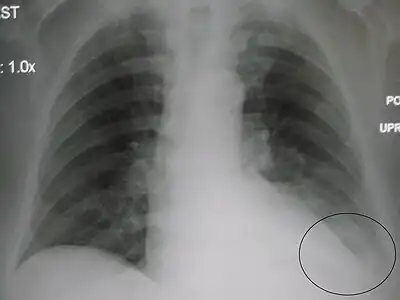

![]() Chest X-ray of a 30-year-old healthy man, with the costodiaphragmatic recess label in red ellipse | |

Pleural effusions collect in the costodiaphragmatic recess when in standing position,[2] and present on plain X-rays as "blunting" of the costophrenic angle.

In anatomy, the costophrenic angles are the places where the diaphragm (-phrenic) meets the ribs (costo-).

Each costophrenic angle can normally be seen as on chest x-ray as a sharply-pointed, downward indentation (dark) between each hemi-diaphragm (white) and the adjacent chest wall (white). A small portion of each lung normally reaches into the costophrenic angle. The normal angle usually measures thirty degrees.

Pleural effusion

With pleural effusion, fluid often builds up in the costophrenic angle (due to gravity). This can push the lung upwards, resulting in "blunting" of the costophrenic angle. The posterior angle is the deepest. Obtuse angulation is sign of disease.

Chest x-ray is the first test done to confirm an excess of pleural fluid. The lateral upright chest x-ray should be examined when a pleural effusion is suspected. In an upright x-ray, 75 mL of fluid blunts the posterior costophrenic angle. Blunting of the lateral costophrenic angle usually requires about 175 mL but may take as much as 500 mL. Larger pleural effusions opacify portions of the hemithorax and may cause mediastinal shift; effusions > 4 L may cause complete opacification of the hemithorax and mediastinal shift to the contralateral side.